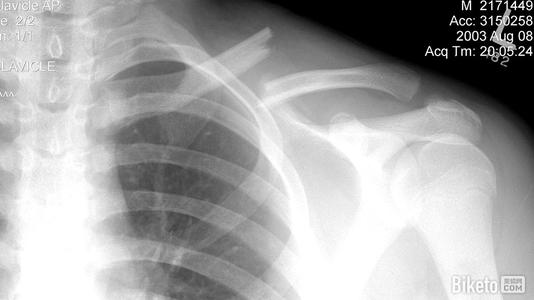

本病的辅助检查方法主要是影像学检查,锁骨骨折常发生在中段。多为横断或斜行骨折,内侧断端因受胸锁乳突肌的牵拉常向上后移位,外侧端受上肢的重力作用向内、下移位,形成凸面向上的成角、错位缩短畸形。

疑有锁骨骨折时需摄X线像确定诊断。一般中1/3锁骨骨折拍摄前后位及向头倾斜45°斜位像。拍摄范围应包括锁骨全长,肱骨上1/3、肩胛带及上肺野,必要时需另拍摄胸片。前后位像可显示锁骨骨折的上下移位,45°斜位像可观察骨折的前后移位。

内侧断端因受胸锁乳突肌的牵拉常向上后移位,外侧端受上肢的重力作用向内、下移位,形成凸面向上的成角

外1/3锁骨骨折中,一般可由前后位及向头倾斜40°位X线像做出诊断。锁骨外端关节面骨折,常规X线像有时难以做出诊断,常需摄断层X线像或行CT检查。